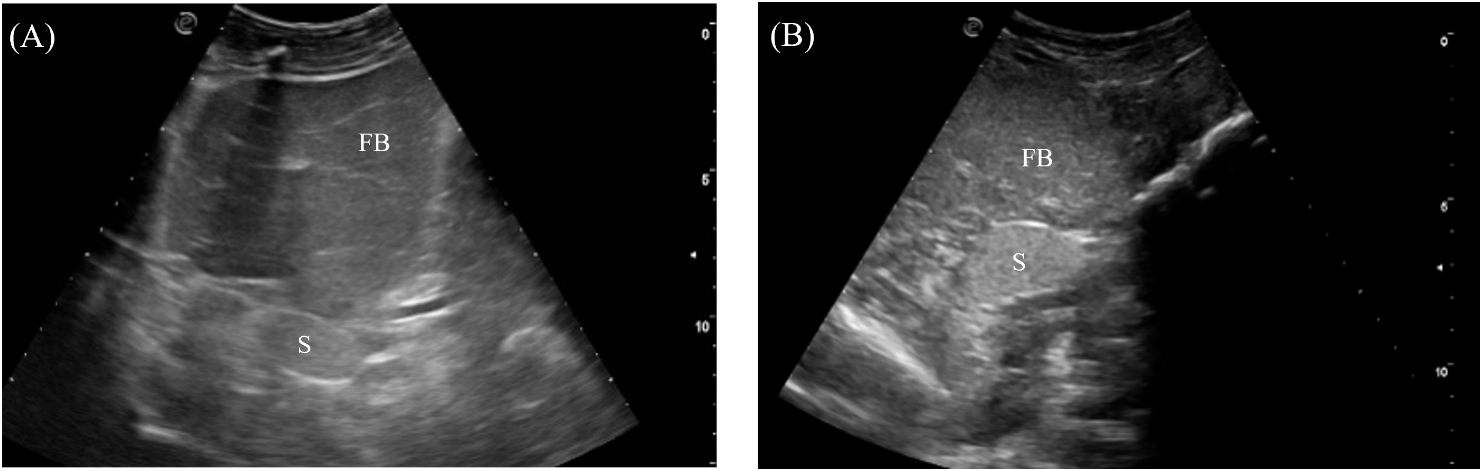

3.3.5 Spleen

The spleen was an ovoid organ positioned mediodorsally in the mid-coelom caudal to the liver lobes (Figure 4). It was visualized in 7/7 crocodilians with the transducer placed on the mid-right flank and directed dorsally (Figure 3, transducer position 7). The spleen was well-marginated with a thin, hyperechoic border. The parenchyma was homogenous and more hyperechoic than the adjacent fat body (Figure 9).

Figure 9

Ultrasonographic appearance of the spleen in (A) sagittal and (B) transverse views from the right lateral approach in Alligator sinensis. [FB, fat body; Sp, spleen].